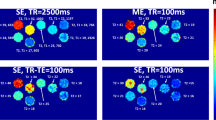

In both LL (Fig. 1a) and MOLLI (Fig. 1b), one or more inversion pulses are followed by a train of read-out segments, sampling the magnetization recovery curves. In LL, a series of low flip angle echo-planar-imaging (EPI) acquisitions is commonly used for readout following an initial IR pulse. Typically, high EPI acceleration and low flip angle are used to avoid saturation of the magnetization recovery. Studies have shown, however, that in flowing blood, the use of higher flip angles can be beneficial due to continuous inflow of unsaturated blood [10, 11].

a Simplified schematic sequence diagram of a Look-Locker (LL) sequence. A 180o inversion pulse used to invert the magnetization from Mz+ to Mz−. Following a waiting time of Timin a readout commences with an excitation pulse “α”, subsequent readout points are performed at Tiinc intervals. In the above case, a total of seven images are acquired with inversion times of Timin + (n – 1 × Tiinc), where n is the image number. Stationary tissue experiences a saturation effect as evident by the solid relaxation curve, while ROIs assessing inflowing blood do not experience this effect, visualised by the dotted line. To change the readout duration the repetition time, in this study given in number of beats, are either increased or decreased. If Tiinc is kept constant, an increase in readout duration also results in an increase in number of sampling points. Increasing the flip angle “α” would increase the saturation effect of stationary tissue, but not that of fast flowing blood. b Simplified sequence diagram of the Modified Look-Locker inversion recovery (MOLLI) sequence. Following a non-selective 180o inversion pulse, the first single shot balanced-SSFP readout is performed at a predefined trigger delay. The resulting image has an inversion time of Timin. For each subsequent cardiac cycle, one image is acquired with the same trigger delay. Tiinc is then defined by the lengths of the following heart cycles. Following the readout of the first inversion pulse (first cycle), a recovery period is allowed, in this example, 2 beats before a second cycle is performed and so on. For each new cycle, position of the inversion pulse is shifted relative to the trigger pulse spreading the sampling points on the recovery curve. In this example, five readouts are performed in the first cycle, followed by a recovery period of 2 beats and then three readouts in the second cycle. This results in the MOLLI scheme of 5(2)3 which has a total scan duration of 10 heartbeats and produces eight images with varying Ti. Increasing the number of beats in the longest cycle effectively increases the readout duration. The density of Ti can be increased, by adding additional cycles and the time allotted for free recovery can be increased by increasing the duration of the recovery period

MOLLI was initially developed to allow for T1 mapping of the heart. The readout is based on the flow-insensitive single-shot-balanced SSFP technique [13] and is fixed in a predefined cardiac phase to allow for pixelwise relaxation assessment. The time between subsequent measurements in MOLLI is then given by the duration of the cardiac cycle. Density of measurements may be increased by adding MOLLI cycles, i.e., repeating the inversion recovery experiment while shifting the timing of the inversion pulse with respect to cardiac phase. The MOLLI scheme 5(3)3 then describes a sequence with five images (one per heart beat) in the first cycle, followed by a pause of 3 heartbeats for magnetization recovery and then a second inversion pulse followed by three images; giving a total of eight inversion recovery sample points, and a breath-hold duration of 11 heartbeats.

Common for both LL and MOLLI sequences is that the magnetization recovery trajectory is influenced by the readout process and this needs to be corrected for to obtain correct \( \widehat{{T_{1} }} \) [8, 9, 14]. In addition, the use of cardiac triggering in both LL and MOLLI can result in a difference in read-out duration and timing of the sampling points based on the patient’s heart rate. For applications outside the heart, cardiac triggering may be less critical, thereby enabling a more flexible timing scheme. Based on the characteristics of the LL and MOLLI sequences, we identify readout duration, sequence timing, and flip angle to be the three main parameters (readily modified by the user) most affecting the quality and accuracy of the resulting T1-maps. These three parameters in the context of T1-mapping sequences will, therefore, be briefly discussed.

Readout duration

In both LL and MOLLI, one or more inversion pulses are followed by a train of readout segments sampling the magnetization recovery curves. The readout duration is defined by the number of triggering beats in LL and the longest cycle in the MOLLI scheme, as described in Fig. 1a, b. Readout duration should not be confused with; the time between inversions, which in LL is close to the readout duration, but higher in MOLLI due to the recovery phase, or the breath-hold time, which in this study is equal to the total scan time of the sequence and dependent on the number of k-space segments in LL and the MOLLI scheme. Increasing the readout duration, and hence number of readout points, gives additional information on the trajectory of the relaxation curve following the inversion pulse, potentially allowing for a more accurate assessment of T1, at the cost of longer breath holds. It is commonly accepted that the readout duration should ideally be in the order of five times T1 and that insufficient delay between inversion pulses could result in a \( \widehat{{T_{1} }} \) bias [15].

Triggering

The MOLLI Native 5(3)3 sequence is a breath-hold technique developed for T1 quantification of non-gadolinium enhanced cardiac tissue. It is based on a flow-insensitive single-shot true-FISP readout using electrocardiogram (ECG) triggering to lock readout to a predefined cardiac phase [9].

Since the time between measurements in MOLLI, and readout duration for both MOLLI and LL is given by the cardiac frequency, a shift in the frequency will change both the timing of sampling points and read-out duration. Such variation has been reported to make \( \widehat{{T_{1} }} \) heart rate dependent [5, 9, 15]. Deactivating ECG-triggering may prevent this dependency in \( \widehat{{T_{1} }} \) when imaging in areas without cardiac motion.

Flip angle

To minimize saturation effects in LL, a series of low flip angle echo-planar imaging (EPI) acquisitions is commonly used. The low flip angle mitigates the saturation effect, but does result in a lower signal-to-noise ratio (SNR) [10]. Studies have shown, however, that in veins and arteries, the use of higher flip angles to increase signal-to-noise ratio is possible due to continuous inflow of unsaturated blood [6, 10, 11].

Comparing the LL sequences with 3 beat readout to those with 5 beat readout (Fig. 5a), we found a lower \( \overline{{T_{{1{\text{s}}}} }} \) (1408 ms vs. 1737 ms, p < 0.001) and a non-significant increase in \( \overline{{CoV_{\text{s}} }} \) (3.24% vs. 2.83%, p = 0.22). Non-triggered sequences performed better in terms of precision than corresponding sequences with ECG-triggering with a significant increase in \( \overline{{T_{{1{\text{s}}}} }} \) (1643 ms vs. 1580 ms, respectively, p < 0.001) and a reduction in \( \overline{{CoV_{\text{s}} }} \) (2.2% vs. 2.9%, respectively, p = 0.0023) (Fig. 5b). Finally, increasing the flip angle from 7o to 45o resulted in an increase in precision with a \( \overline{{CoV_{\text{s}} }} \) reduction from 4.35 to 2.5%. (p < 0.001) (Fig. 5c) and a decrease in T1 from 1593 to 1574 ms, (p = 0.01).

Comparison of the CoV by individual parameters. The difference in CoV caused by readout duration a timing method, b flip angle, c shows a significant decrease in CoV for timing method (CoV 2.9% vs. 2.2%, paired samples t test p = 0.0023) and flip angle (CoV 4.35% vs. 2.5% p < 0.001). The decrease caused by increasing readout duration was, however, not significant (CoV 3.24% vs. 2.83%, paired samples t test p = 0.22)